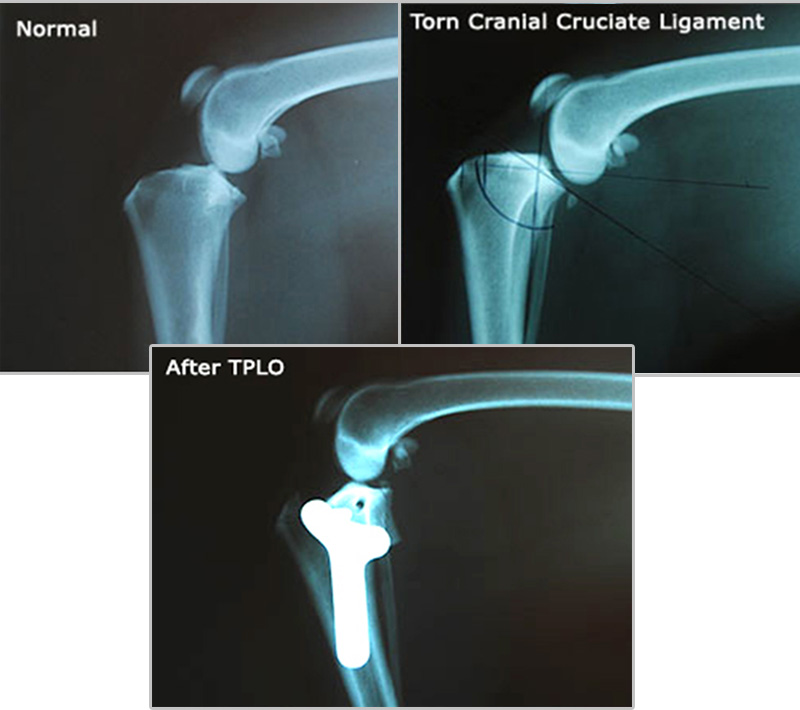

The illustrations below demonstrate how the TPLO surgery works:

- Postoperative Xrays are taken to assess the new tibial plateau angle and verify correct positioning of the plate and screws. In the X-rays below, the leg has been corrected by TPLO, and the femur is now resting securely on top of the tibia, in a similar position to the normal joint.